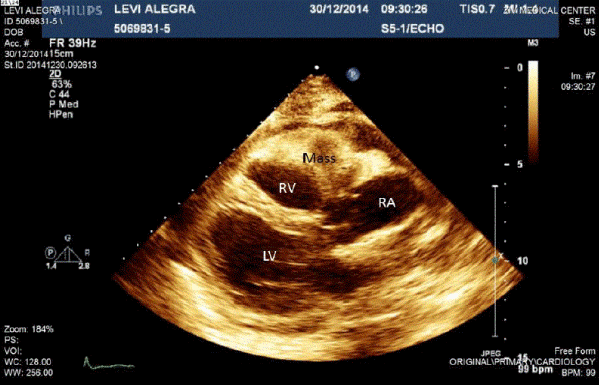

A 63-year-old woman with a medical history of smoking and epilepsy was hospitalized after a two-week period of shortness of breath. Her physical examination was notable for tachycardia and distant heart sounds. She underwent a transesophageal echocardiogram which showed a large mass engulfing the right ventricle and atrium, infiltrating the free wall of the ventricle into the tricuspid valve and compressing the superior vena cave (Figure 1). A chest CT revealed a large mass infiltrating the right ventricle and atrium and intruding the SVC (Figure 2). She was hemodynamically stable. A multidisciplinary team decided that a biopsy was necessary. The post-operative course was uneventful. The biopsy specimen showed a diffuse large B-cell lymphoma (Figure 3). Chemotherapy was immediately started.

Figure 1. Transesophageal echocardiogram - Parasternal long axis view with the mass attached to the RV and RA